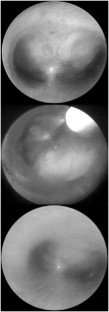

We report the first case to be observed in a neonate of an intramural bronchogenic cyst in the carina. Considering the age of the infant, it was decided to administer curative treatment by needle aspiration. A rigid bronchoscopy was used. The outcome was favorable.

Gaugler, C., Donato, L., Rivera, S. et al. Intramural Bronchogenic Cyst in the Carina Observed in a Neonate and Treated by Needle Aspiration: A Case Report. J Perinatol 24, 317–318 (2004). https://doi.org/10.1038/sj.jp.7211089